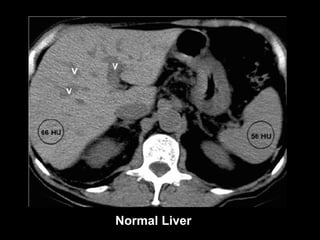

Diagnosis at CT Normal Liver The normal liver has slightly greater attenuation than the spleen and blood. Intrahepatic vessels are visible as hypoattenuated structures Fatty liver Unenhanced CT Attenuation of the liver is at least 10 HU less than that of the spleen or attenuation of fatty liver is less than 40 HU In severe cases, intrahepatic vessels may appear hyperattenuated relative to fat-containing liver tissue.

Normal Liver